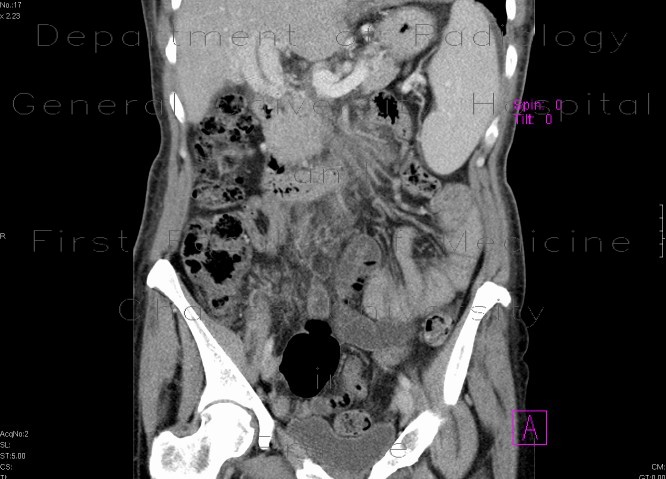

An enhancing lesion in the hepatoduodenal ligament tracking along biliary ducts into the liver.

Radiology image - Portal cavernoma: Abdomen, Liver: CT - Computed tomography

Portal cavernoma: CT - Computed tomographyPortal cavernoma: CT - Computed tomographyPortal cavernoma: CT - Computed tomographyPortal cavernoma: CT - Computed tomographyPortal cavernoma: CT - Computed tomography